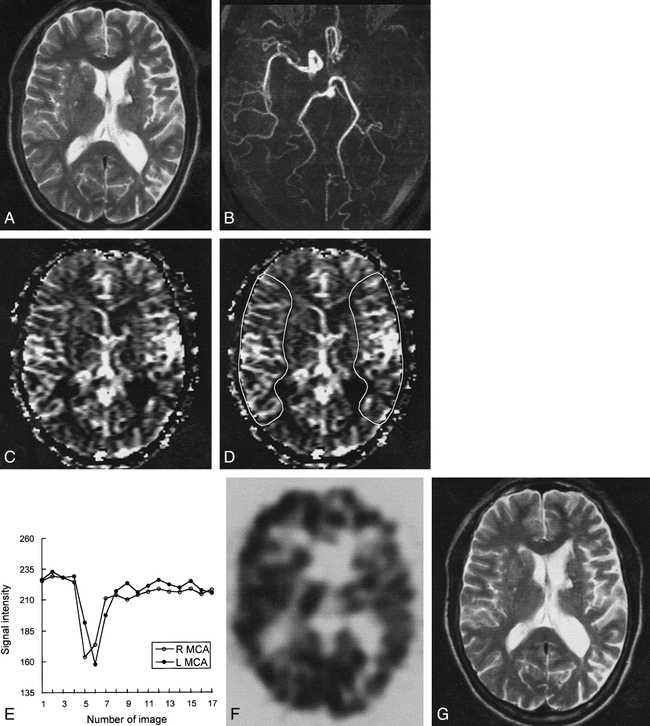

Case 10: 61-year-old man with hyperacute ischemic stroke with arterial occlusion and increased CBV.

A, T2-weighted image (3500/90) is normal except for small chronic lesion with hemosiderin rim in left basal ganglia.

B, 3D time-of-flight MR angiogram reveals occlusion of left internal carotid artery through M1 segment of the left MCA.

C, CBV map shows increased CBV throughout left MCA distribution.

D, CBV map shows irregular ROIs placed for measurement of CBV ratio and time–signal intensity curves between the region of increased CBV and contralateral normal region. Calculated CBV ratio was 1.23.

E, Time–signal intensity curves measured during passage of contrast material show delayed arrival time and delayed washout of the contrast material in left MCA distribution, suggesting collateral flow.

F, 99mTc-HMPAO brain SPECT scan obtained during the hyperacute stage at approximately the same level as A and C reveals mild hypoperfusion throughout left MCA and anterior cerebral artery distribution.

G, Follow-up T2-weighted MR image (3500/90) obtained 2 days after the onset of symptoms is normal except for small chronic lesion in left basal ganglia.

Time–signal intensity curves showed no reduction of signal intensity in the region of decreased CBV in any of the eight patients with the pattern of arterial occlusion and decreased CBV (Fig 1E). In two patients with the pattern of arterial occlusion and increased CBV, delayed arrival time and delayed washout of the contrast material in the region of increased CBV was observed, suggesting recruitment of blood flow through collaterals (Fig 2E). In two patients with the pattern of no arterial occlusion and normal CBV, there were no differences in signal reduction, arrival time, or washout pattern of the contrast material between the hemispheres.

Brain SPECT was performed in nine of 12 patients. The mean CBF ratios measured on SPECT were 0.39 (range, 0.20–0.65) in six patients with the pattern of arterial occlusion and decreased CBV (Fig 1F), 0.85 (range, 0.81–0.89) in two patients with the pattern of arterial occlusion and increased CBV (Fig 2F), and 0.99 in one patient with the pattern of no arterial occlusion and normal CBV. Although CBF ratios in these three imaging patterns were obviously different, there was no statistically significant difference, owing to the small number of patients (P = .061 by Kruskal-Wallis test).

Follow-up CT or MR examinations in all eight patients with the pattern of arterial occlusion and decreased CBV showed infarctions, whose extent correlated well with the region of CBV and CBF abnormalities (Fig 1G). In two patients with the pattern of arterial occlusion and increased CBV, infarctions did not develop on initial follow-up images (Fig 2G). The development of infarctions was statistically significantly different between these two patterns (P = .022 by Fisher's exact test). In one patient (case 9), however, watershed infarction developed in the cerebral deep white matter 3 days after the first follow-up study. In two patients with the pattern of no arterial occlusion and normal CBV, follow-up imaging was not performed.